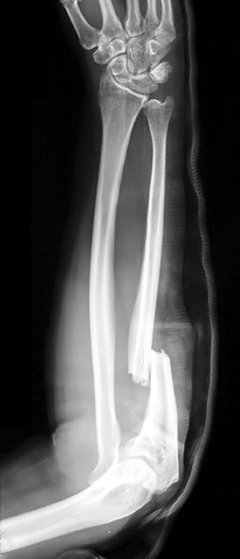

Example 2

Diagnosis

Smith’s Fracture